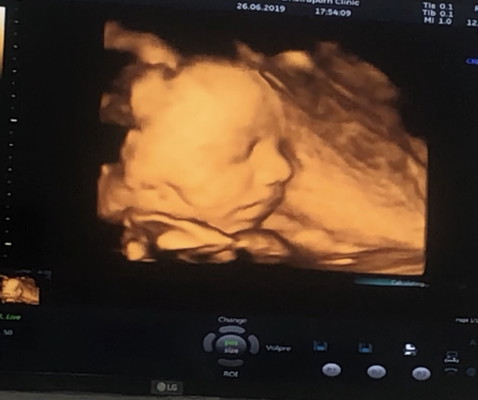

11 กันยา ผู้ชายครับ รูปซาวด์ตอน 26 วีค ตอนนี้ 29 วีคแล้วครับ👶